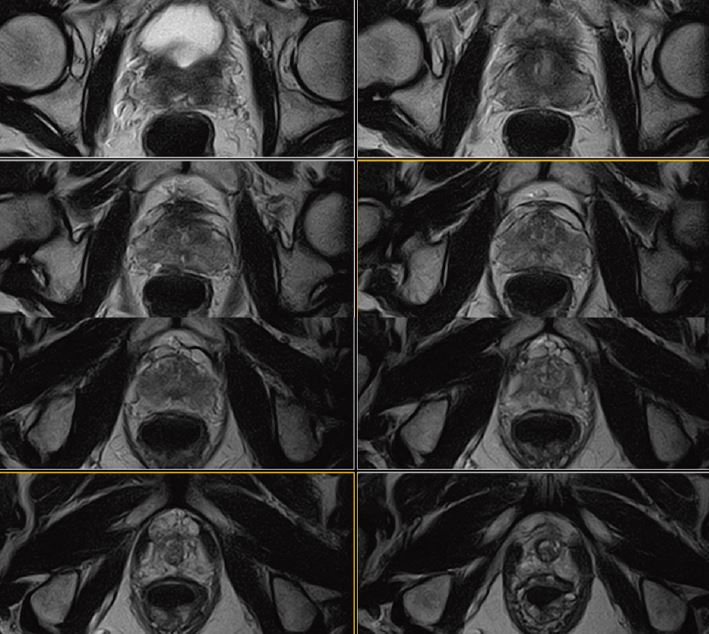

Рис. 7. Аксіальне DWI – A=b0, B=Iso b800, C=Iso b1000 e, D=Iso ADC (за протоколом mpMR)

Рис. 8. Динаміка. Аксіал (12 фаз): A=1a phase pre, B=3a phase pos, C=6a phase pos, D=12a phase (за протоколом mpMR) .

Рис. 10. Аксіальне, Т2-зважене зображення (за протоколом mpMR).

Рис. 11. Аксіальне DWI – A=b0, B=Iso b800, C=Iso b1000 e, D=Iso ADC (за протоколом mpMR).